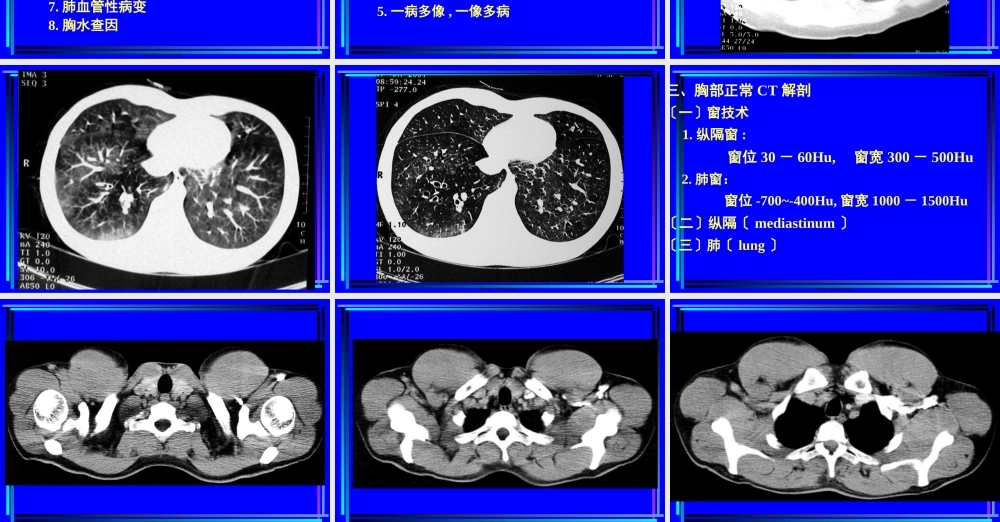

胸部CT诊断第一节胸部CT检查一、胸部CT扫描方法〔一〕普通扫描〔平扫plainCTscan〕第一页,共二百二十九页。第二页,共二百二十九页。第三页,共二百二十九页。第四页,共二百二十九页。〔二〕增强扫描〔contrastenhancement,CE〕1.注药方法团注法〔bolusinjection〕静滴法2.扫描程序静态CT扫描动态CT扫描〔dynamicCTscan〕第五页,共二百二十九页。第六页,共二百二十九页。〔三〕特殊扫描1.薄层扫描2.高分辨率CT扫描〔HighresolutionCT,HRCT〕3.CT血管造影〔CTangiography,CTA〕4.心电门控扫描第七页,共二百二十九页。第八页,共二百二十九页。第九页,共二百二十九页。第十页,共二百二十九页。第十一页,共二百二十九页。第十二页,共二百二十九页。第十三页,共二百二十九页。二、CT对胸部疾病的诊断价值与限度〔一〕诊断价值1.肺部小病灶与早期病变2.咯血查因3.肺不张、肺实变4.肺肿瘤分期5.肺弥漫性病变6.肺气肿的诊断及功能评价7.肺血管性病变8.胸水查因第十四页,共二百二十九页。〔二〕影响CT检出与诊断的因素〔主要为常规CT〕1.运动伪影2.局部容积效应3.层厚与层间距4.大量胸水5.一病多像,一像多病第十五页,共二百二十九页。第十六页,共二百二十九页。第十七页,共二百二十九页。第十八页,共二百二十九页。三、胸部正常CT解剖〔一〕窗技术1.纵隔窗:窗位30-60Hu,窗宽300-500Hu2.肺窗:窗位-700~-400Hu,窗宽1000-1500Hu〔二〕纵隔〔mediastinum〕〔三〕肺〔lung〕第十九页,共二百二十九页。第二十页,共二百二十九页。第二十一页,共二百二十九页。第二十二页,共二百二十九页。第二十三页,共二百二十九页。第二十四页,共二百二十九页。第二十五页,共二百二十九页。第二十六页,共二百二十九页。第二十七页,共二百二十九页。第二十八页,共二百二十九页。第二十九页,共二百二十九页。第三十页,共二百二十九页。第三十一页,共二百二十九页。第三十二页,共二百二十九页。第三十三页,共二百二十九页。第三十四页,共二百二十九页。第三十五页,共二百二十九页。第三十六页,共二百二十九页。第三十七页,共二百二十九页。第三十八页,共二百二十九页。第三十九页,共二百二十九页。第四十页,共二百二十九页。第四十一页,共二百二十九页。第四十二页,共二百二十九页。第四十三页,共二百二十九页。第四十四页,共二百二十九页。第四十五页,共二百二十九页。第四十六页,共二百二十九页。第四十七页,共二百二十九页。第...